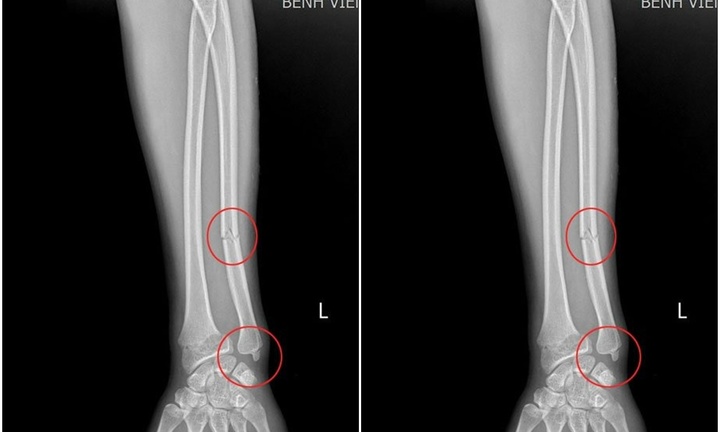

Tờ Pháp luật & Xã hội đưa tin BSCKI Mai Thành Nam - Phó trưởng khoa phụ trách Khoa Chăm sóc sức khỏe sinh sản & Phụ sản là người trực tiếp thực hiện ca mổ. Khi lấy em bé ra, các bác sĩ vô cùng bất ngờ khi thấy dây rốn thắt nút chặt ở tay và quấn quanh người bé.

Nhờ sự chuẩn bị kỹ lưỡng và phối hợp nhịp nhàng, ê-kíp đã nhanh chóng tháo gỡ dây rốn, giúp em bé thoát khỏi nguy hiểm.

May mắn, bé gái chào đời an toàn, nặng 2,9kg và hoàn toàn khỏe mạnh. Tiếng khóc chào đời của bé đã khiến cả ê-kíp y tế thở phào nhẹ nhõm và vỡ òa trong niềm vui.

Theo chia sẻ của người mẹ khi còn trong bụng, bé rất nghịch ngợm. Ngay sau khi chào đời, bé vẫn không ngừng cử động, đưa tay huơ huơ trước mặt. Điều này phần nào giải thích vì sao chỉ trong vòng một tuần, dây rốn đã quấn thêm vài vòng quanh người bé.